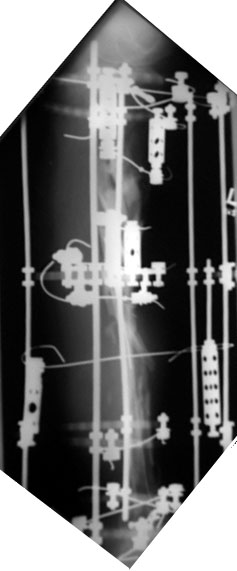

Nine Month Followup.Click images to enlarge.

Patient is 30 yo male 9 months status post severely comminuted tibia fracture (plateau, shaft, plafond) treated with ring fixator and free flap. Soft tissue coverage good. 10 wks since last procedure (bone graft plus additional wires). The pin tracts are OK. Minimal callus.